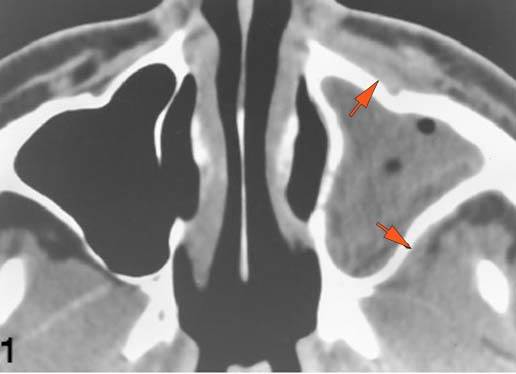

The extraconal orbital fat is abnormal. [Yes/No]

There is a subperiosteal abscess or edema along the medial wall, roof or floor of the orbit. [Yes/No]